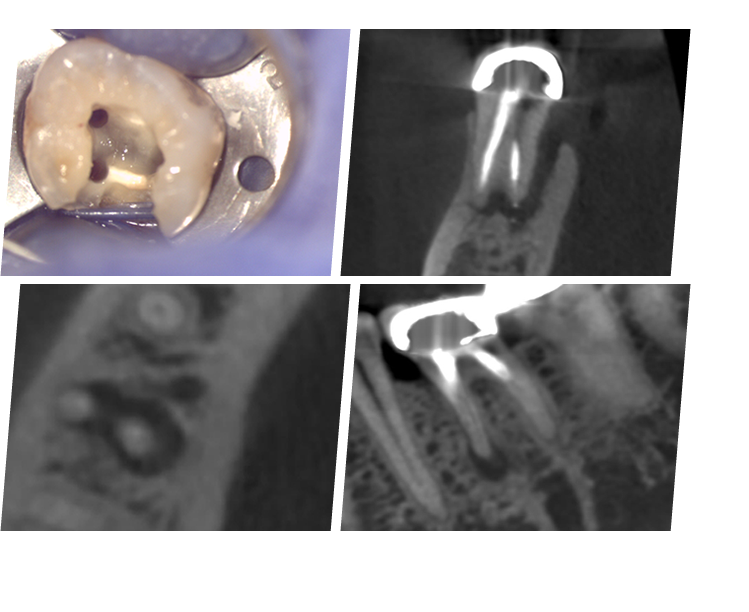

牙齒根管型態是非常複雜,許多根管失敗案例幾乎都是根管殘留感染源造成,部分是穿孔(Perforation)顯微鏡的優點是高倍率下很容易看清楚根管3D構造,必須配合許多顯微器械,有效移除齒質,減少牙齒過度破壞,甚至減少根尖手術的機率,達到保留牙齒最大目的。